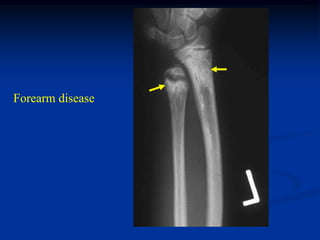

Case #572

15 year female

Ollier’s disease

AP close up knee

Forearm disease